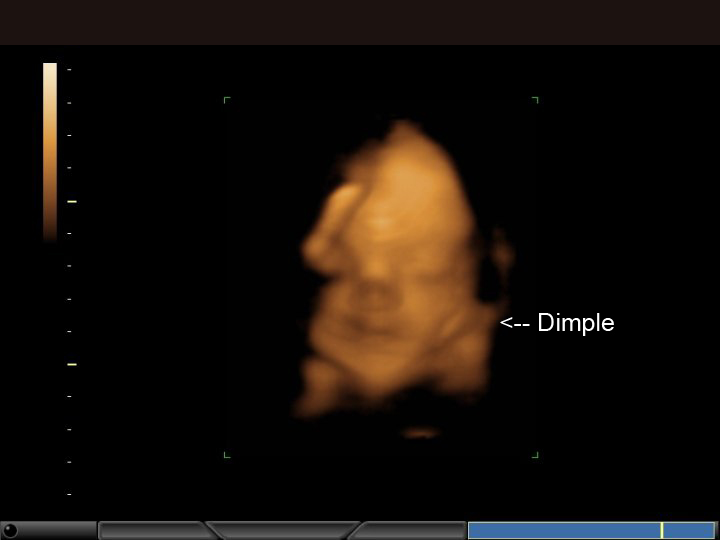

Two weeks ago, at 28 weeks, we had our 3D ultrasound. It was great fun! We confirmed that baby is in fact a boy, and got to see his cute little face. We came away with some photos and a video. It was really neat. I couldn't figure out how to get the video clips on here, but here are some of the stills:

One more cute face shot. Looks like he has mom's dimples: